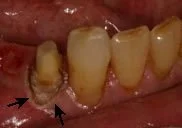

Before Crown Lengthening

This tooth required crown lengthening to provide enough tooth surface for a restoration